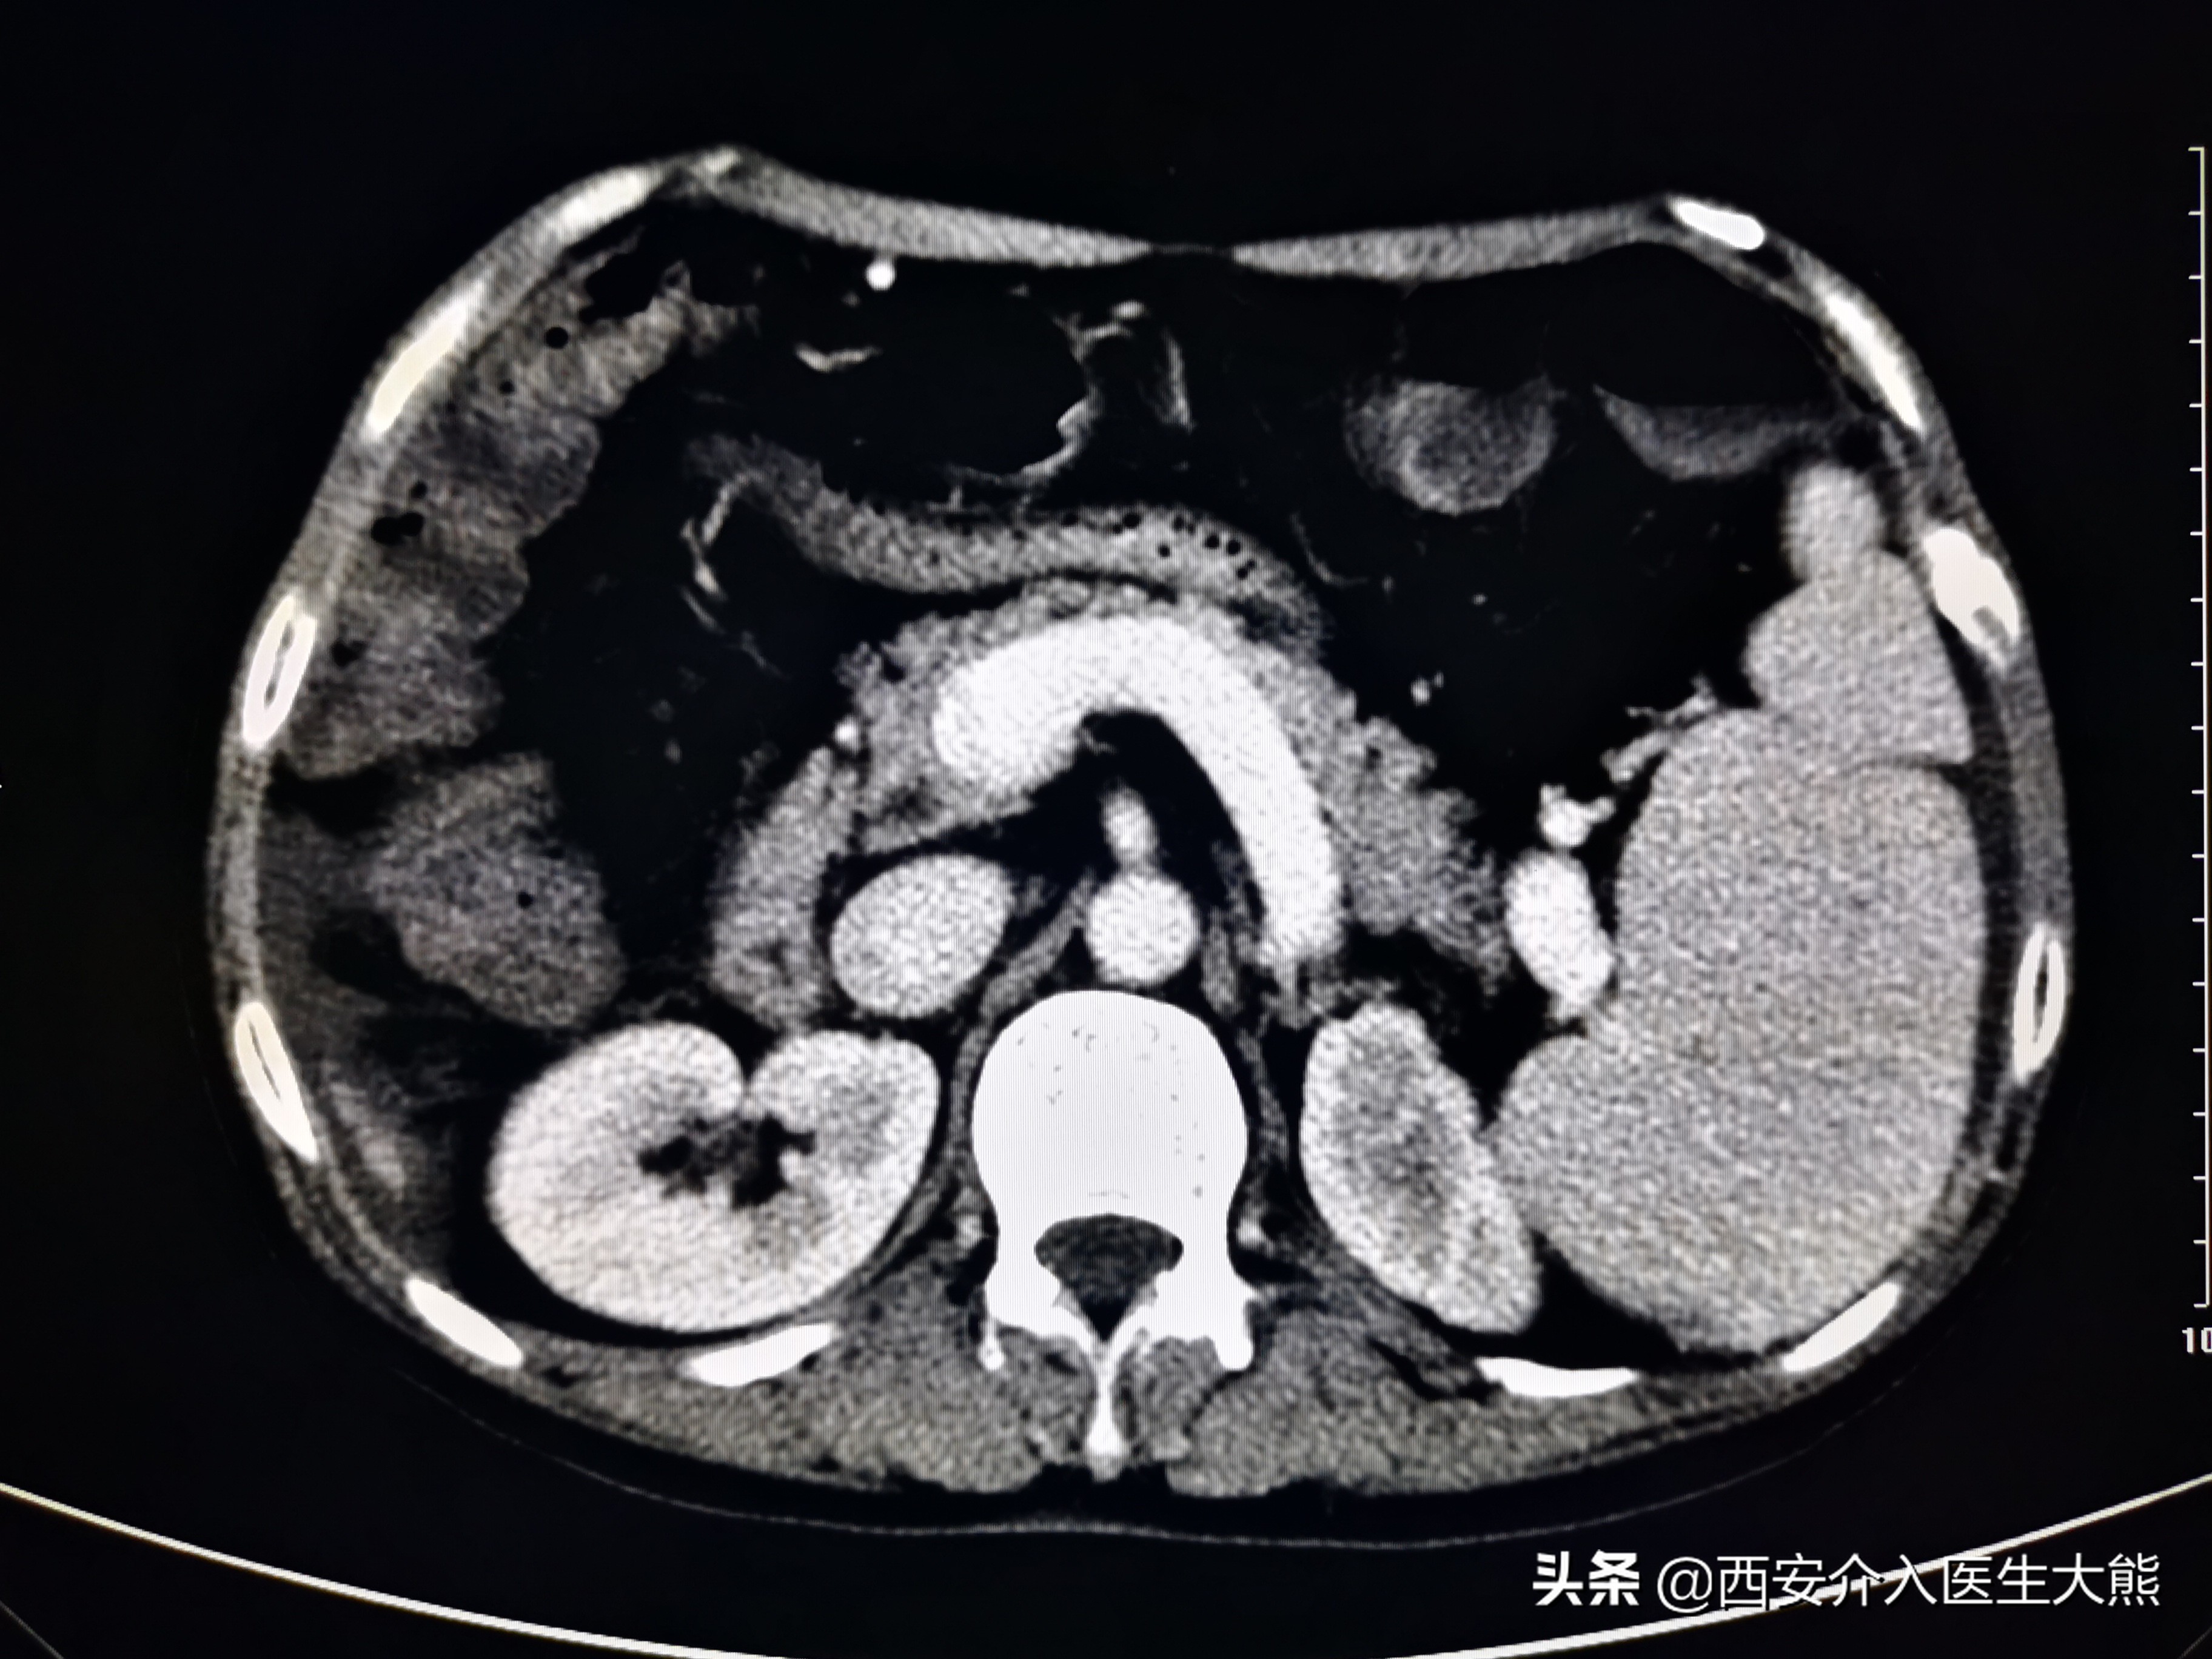

1、CT(2021-11-8):(1)、肝硬化(脾大、门静脉高压、食管胃底静脉曲张,门静脉高压。胆汁淤积,胆囊壁水肿性改变;左肾萎缩,左肾盏结石;(4)、膀胱导尿术后改变;子宫显示不清;直肠CT平扫未见异常。

扩张的脐静脉

扩张的没静脉和胃冠状静脉

扩张的胃冠状静脉

这名患者的治疗过程就符合该治疗策略。术前的CT平扫已经显示极度扩张的胃冠状静脉,这在DSA影像上得到证实。2018年患者第二次出血时做的增强CT上已经显示出患者的胃冠状静脉扩张。此时,已经具有行TIPS的指征。在经过3年的变化后,病情是急剧加重。如果出血剧烈、生命体征不平稳,或各种原因导致不能行急诊胃镜的情况下,不要错过TIPS降低门脉压力的机会。

胃镜和增强CT是评估患者病情的重要措施。该患者由于病情严重,每一次搬动,都增加了患者再次出血的风险,所以未能完善这2项检查。但是CT平扫的结果证实门静脉及属支的扩张,在某种程度上替代了胃镜的作用。但是不能忽视的是,仍有部分患者可能是消化道溃疡导致出血。根据目前指南的推荐,在病情允许的情况下,应该尽早完善胃镜检查和增强CT。如果病情不允许,普通CT平扫亦能提供部分诊疗信息。